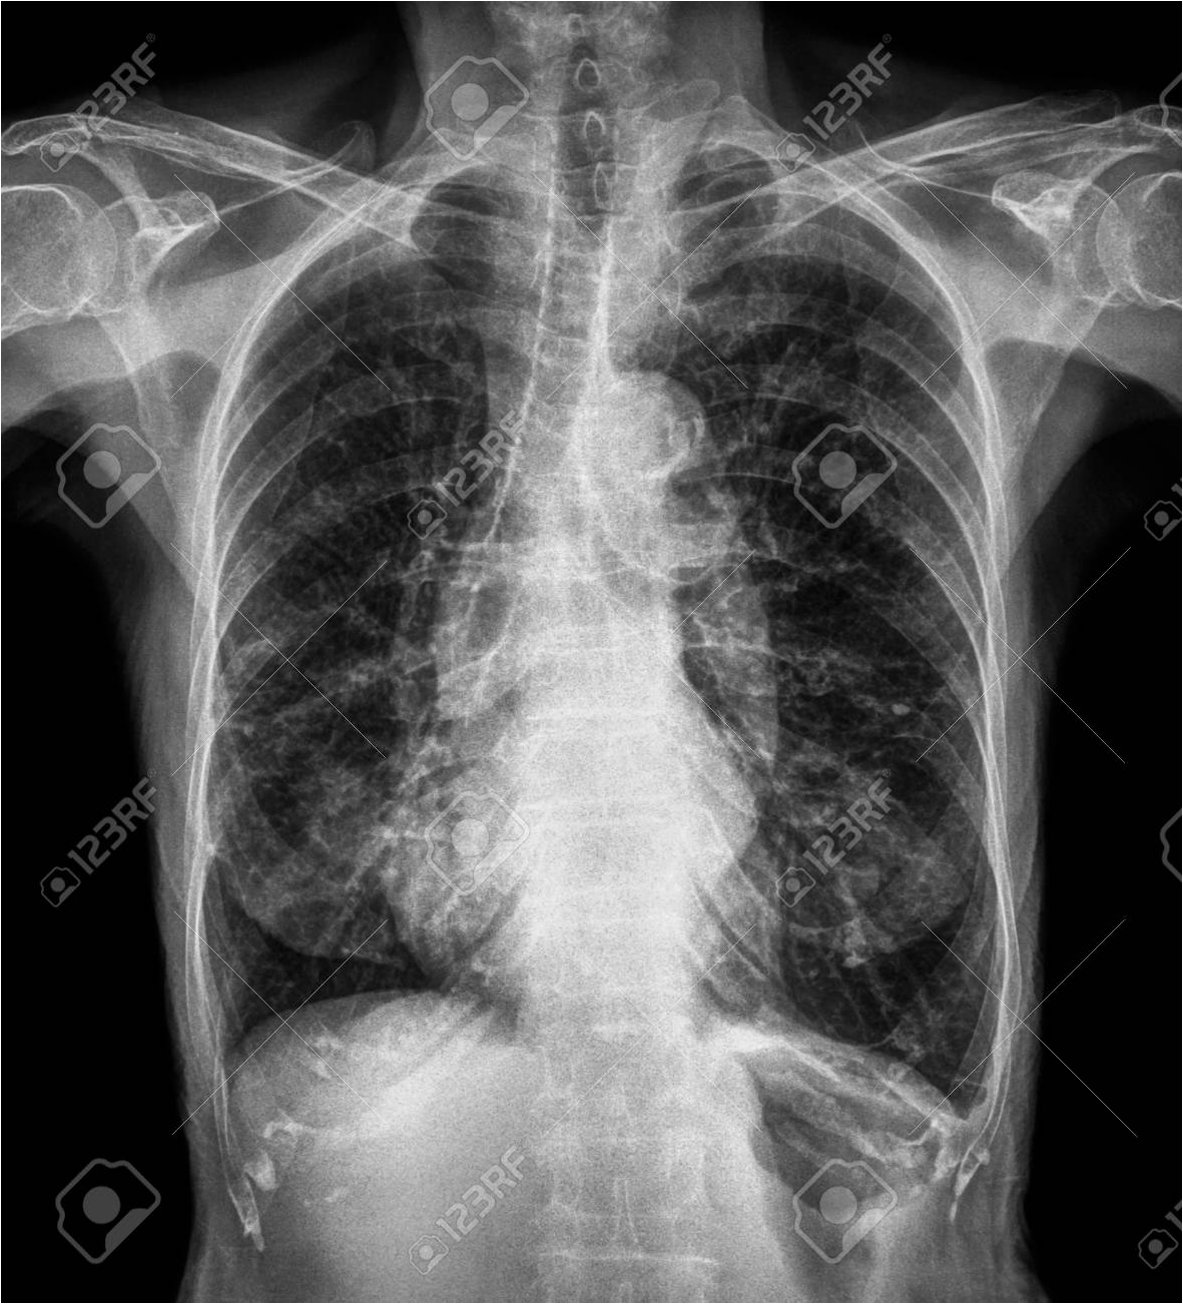

사고 발생 5년 뒤인 2019년부터 밤마다 원인 불명의 고열에 시달리던 사이먼스 씨는 병원을 찾았습니다. CT 검사 결과, 사고 당시 흡입했던 먼지 파편이 폐 깊숙이 들어가 배출되지 못하고 딱딱하게 굳어 왼쪽 폐 기관지를 완전히 막고 있다는 충격적인 사실이 밝혀졌습니다. 그는 '기계에 깔려 움직일 수 없을 때 먼지를 들이마셨는데, 그게 깊이 들어가 굳어버렸다'고 당시를 설명했습니다.

의료진은 이물질이 기관지에 박히면서 신체가 칼슘으로 둘러싸 격리하는 과정에서 석회화가 진행된 것으로 판단했습니다. 정밀 검사 결과, 좌측 폐는 5년간의 감염으로 기능을 완전히 상실한 상태였습니다. 의료진은 처음에는 석회화된 부분만 제거하려 했으나, 손상 범위가 너무 넓어 결국 폐 전체를 적출해야 한다는 결론에 이르렀습니다. 사이먼스 씨는 결국 왼쪽 폐를 떼어내는 수술을 받았습니다.